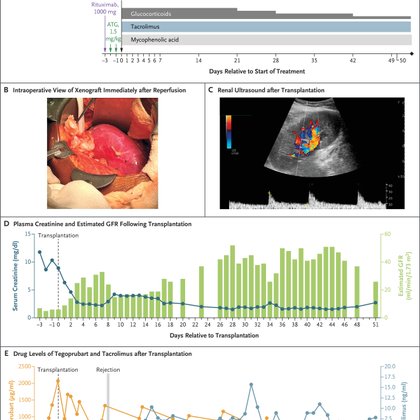

🚨BREAKING: Our report on the first-ever pig kidney xenotransplant in a living human with ESRD is now published in @NEJM! A major milestone in transplantation, paving the way for a new era of organ replacement @mgh_transplant @MGHKidneys @eGenesisBio more:

Xenotransplantation offers a potential solution to the organ shortage crisis. A 62-year-old hemodialysis-dependent man with long-standing diabetes, advanced vasculopathy, and marked dialysis-access...